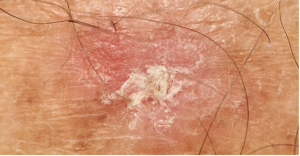

In the final part of this Frontline Forum series, Brent Moody, MD; Sarah Arron, MD, PhD; Justine Cohen, DO; Emily Ruiz, MD, MPH; and Todd Schlesinger, MD, review 4 real-world clinical cases of BCC and the treatments they utilized.